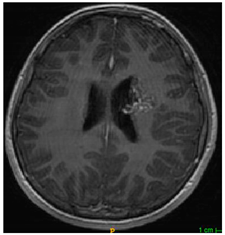

Three cases from the NTUH dataset showing representative results of different models were shown in Table 2, Table 3 and Table 4. The overall dice scores of these networks on the NTUH dataset ranged from 0.33 (DeepMedic) to 0.51 (V-Net). Table 5 shows the detailed performance of each network tested with the NTUH dataset.

Table 2.

Predictions with low dice scores.

Table 3.

Predictions with average dice scores.

Table 4.

Predictions with high dice scores.